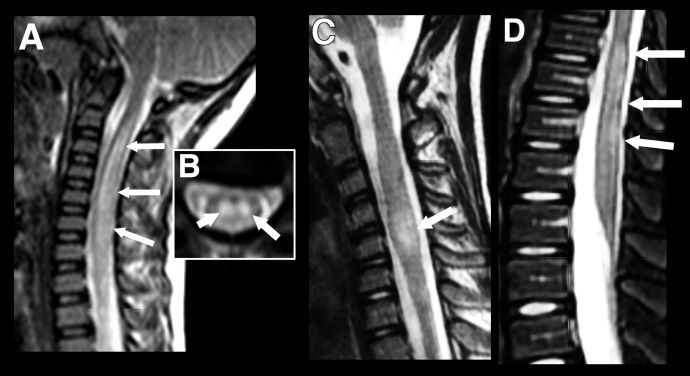

Pediatric patients can present with longitudinally extensive transverse myelitis (LETM) which can occur as part of a wider spectrum of disease or rarely as an isolated presentation. It is defined as a T2-hyperintensity which occurs over three or more vertebral segments (Figure 4). In children it is most often associated with an ADEM phenotype or NMOSD and normally involves the cervical region of the spine.[21] While short (<3 vertebral segments) transverse myelitis has been reported within the context of pediatric MOGAD it is a rarer disease phenotype than that seen in adults (Figure 4). [22] In general, gadolinium enhancement of lesions in pediatric MOGAD patients is less prominent than in adults and, where present, is often diffuse and not confined to discrete, patchy lesions as seen in adults.[23]

Figure 4 Longitudinally extensive transverse myelitis (LETM) vs Short transverse myelitis. Imaging findings in transverse myelitis in pediatric MOGAD in the acute phase. A: Sagittal T2-weighted image showing longitudinally extensive transverse myelitis, with increased signal and marked swelling of the cervical cord. Corresponding mid-cervical axial image (B) shows typical central cord involvement. Comparison case from another child shows a short segment cervical transverse myelitis, but this also involves the central cord (C, sagittal T2-weighted image) as well as a more typical longitudinally extensive transverse myelitis in the lumbar cord (D).